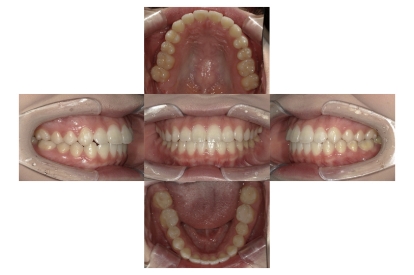

症例2

上下顎前突、叢生

抜歯

ブラケット矯正

上下顎前突、叢生(上下出っ歯、上下の前歯のガタガタ)のケースです。

装置はラビアル(上下表側)で、上下顎の小臼歯を4本抜歯を行っています。抜歯したスペースを使って、上下の前歯の後方移動と叢生(ガタガタ)の改善を行っています。

主訴 前歯のガタガタと口元がでているのが気になる。

年齢・性別 30歳 女性

お住まいの地域 東京都大田区

治療方針 抜歯スペースを利用して上前歯の叢生(ガタガタ)と口元突出の改善

抜歯部位 上下顎左右第一小臼歯

使用装置 ラビアル(上下表側)、顎間ゴム

治療期間 1年11か月

治療回数 13回

リテーナー クリアリテーナー

AFTER